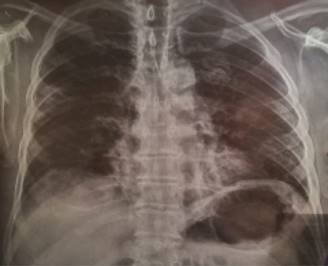

El paciente presentó aumento de trabajo respiratorio, se tomó radiografía de tórax (Figura 1) con opacidades heterogéneas periféricas de ambos pulmones, comportándose como neumonía por COVID-19 y se solicitó tomografía simple de tórax (TC) donde se observa imagen de vidrio despulido en las periferias pulmonares, zonas de consolidación y atelectasias (Figura 2). Los laboratorios iniciales con leucocitos de 11,200, neutrófilos de 88% y linfocitos de 8%, hemoglobina (Hb) 14 g/dL, hematocrito (Hto) 42.2%, plaquetas de 359,000, PCR 96, DHL de 684. Se recaba prueba RT-PCR positiva, se agrega disnea progresiva e hipoxemia requiriendo manejo avanzado de la vía aérea.

Figura 1: Radiografía simple de tórax donde se observan opacidades heterogéneas periféricas de ambos pulmones. Día del estudio 27 de marzo de 2020.